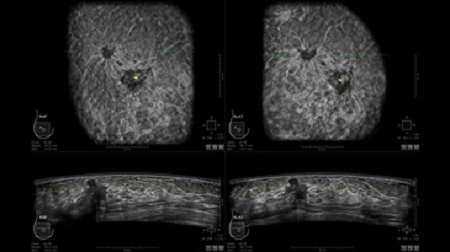

• Получение объемных 3D изображений с возможностью покадрового просмотра

• Алгоритмы обработки изображений: алгоритм однородности изображения ткани (TEA), подавление зернистости, компенсация акустической тени от соска (NSC), определение границ молочной железы (BBD), определение стенки грудной клетки

• Получение изображений в поперечной плоскости (в реальном времени) и в коронарной плоскости (статическая, для указания нахождения соска)

• Отображение объемных 3D ультразвуковых изображений, которые состоят из традиционных поперечных и воссозданных коронарных и сагиттальных проекций

• Стандартизованная ориентация изображения: «толстый срез» в коронарной плоскости; поперечная; сагиттальная плоскость; радиальный и антирадиальный поворот изображения; просмотр исключительно области интереса

• 360 ° APC - отображение области по «любой точке компаса»